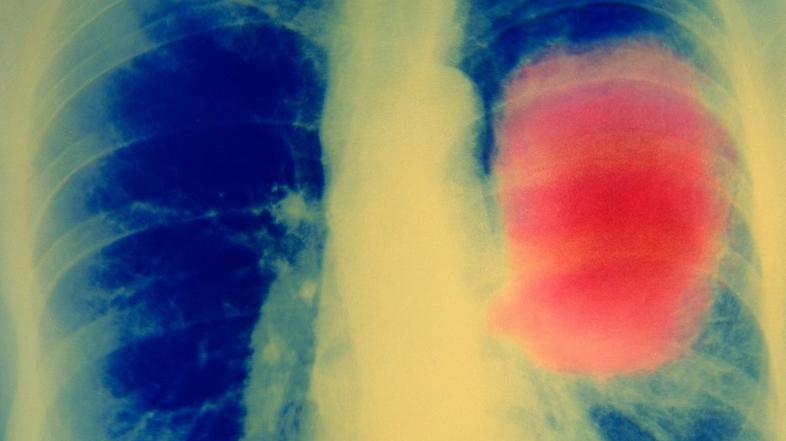

Rak na pljučih Profimedias

"Umrljivost kadilcev je dva do trikrat večja od umrljivosti oseb, ki niso nikoli kadile. Pljučni rak, srčno-žilne bolezni in kronična obstruktivna pljučna bolezen (KOPB) povzročijo največ smrti, povezanih s kajenjem, a spisek s kajenjem povezanih bolezni se vedno znova podaljšuje," je opozorila Mihaela Zidarn s Klinike Golnik.